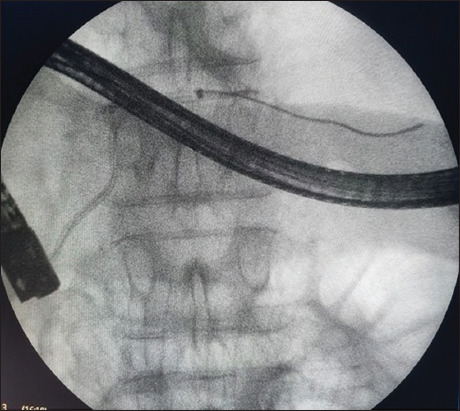

Abstract Image